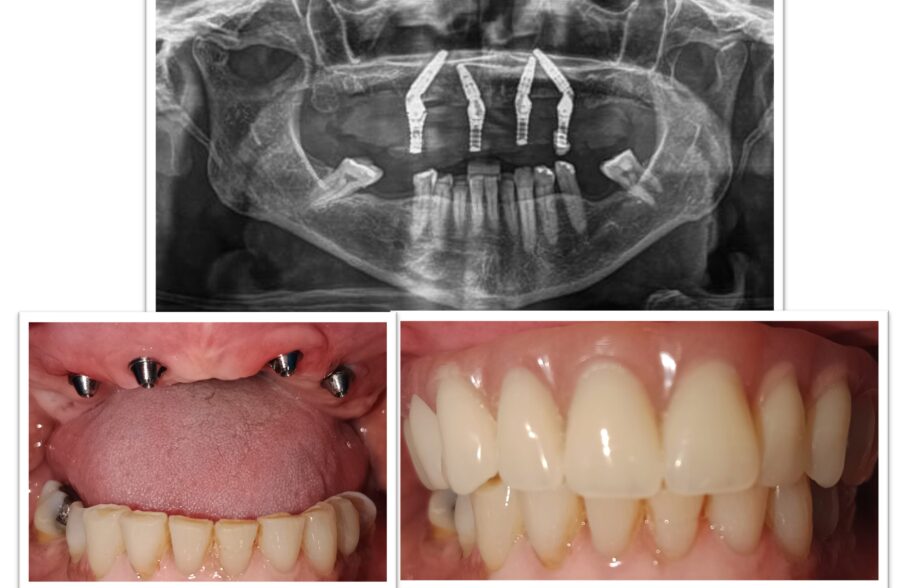

Cirugía oral y maxilofacial